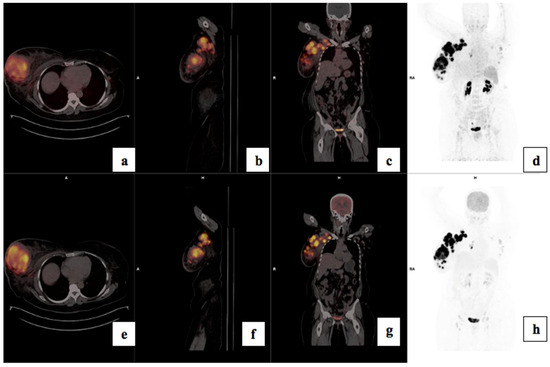

3.5. Treatment Response